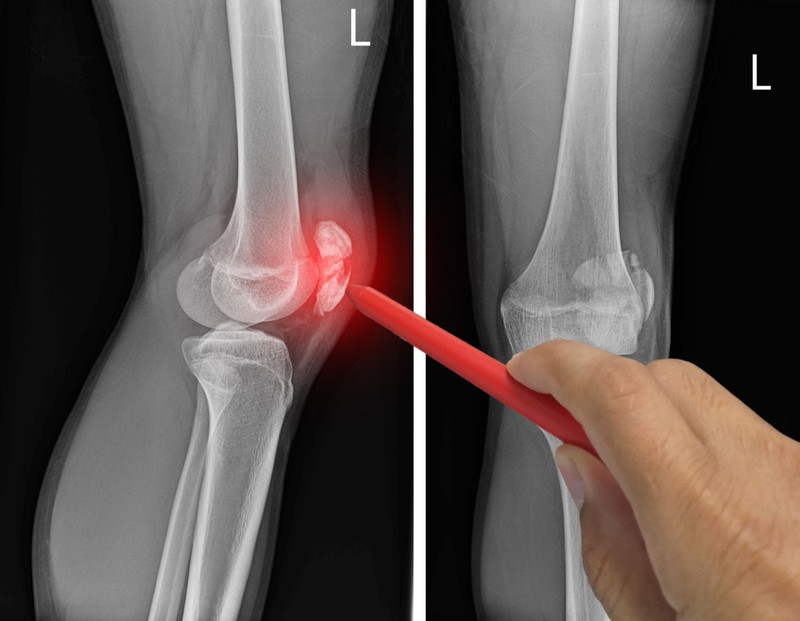

Porckopás: így lehet a térdfájást megelőzni sportolással

Ha már kialakult a porcprobléma sincs minden veszve.